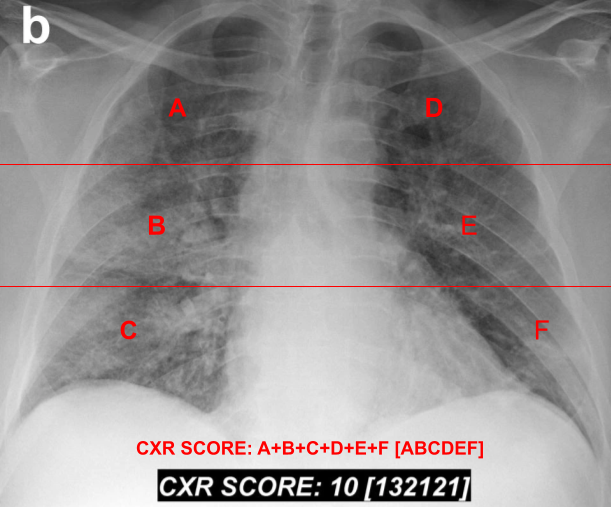

To compare our stacked DNN analysis with radiologists’, we will use the Brixia score. This scoring system, presented in Borghesi and Maroldi (2020), was created to grade the severity of Covid-19 cases. To score a chest X-ray, the radiologist divides the lungs into 6 parts, using two horizontal lines. The upper line is drawn at the inferior wall of the aortic line, and the other line at the level of the right pulmonary vein. If it is difficult to identify the anatomical landmarks, the authors suggest dividing the lungs into three equal zones. For each of the 6 zones, the radiologist attributes a partial score, from 0 to 3, with higher values indicating higher severity. 0 means no abnormalities in the zone, 1 means interstitial infiltrates, 2 interstitial and alveolar infiltrates, with interstitial predominance, and 3 interstitial and alveolar infiltrates, with alveolar predominance. The lines and the 6 regions are illustrated in Figure 11. Note that a single letter in red (A, B, C, D, E or F) represents a partial score for one of the 6 regions. The overall Brixia score (from 0 to 18) is the sum of the partial scores (A+B+C+D+E+F). After the overall Brixia score, the 6 partial scores are presented, between square brackets, from A to F ([ABCDEF]). At the bottom of Figure 11, we show in red how the score is presented. Below it, in white, there is the real Brixia score for the X-ray, which presents a 72-years-old male diagnosed with Covid-19, 4 days after hospitalization. The X-ray was scored by radiologists and is presented in Borghesi and Maroldi (2020). The system authors discovered that the score of later deceased patients was significantly higher than from discharged patients (Borghesi and Maroldi (2020)).

Refer to caption

Figure 3: Illustration of the lung zones for the Brixia score, and how the score is presented (bottom), based in Borghesi and Maroldi (2020). The Brixia score, attributed by radiologists, is presented in white. The X-ray presents a 72-year-old man with Covid-19 in the fourth day of hospitalization